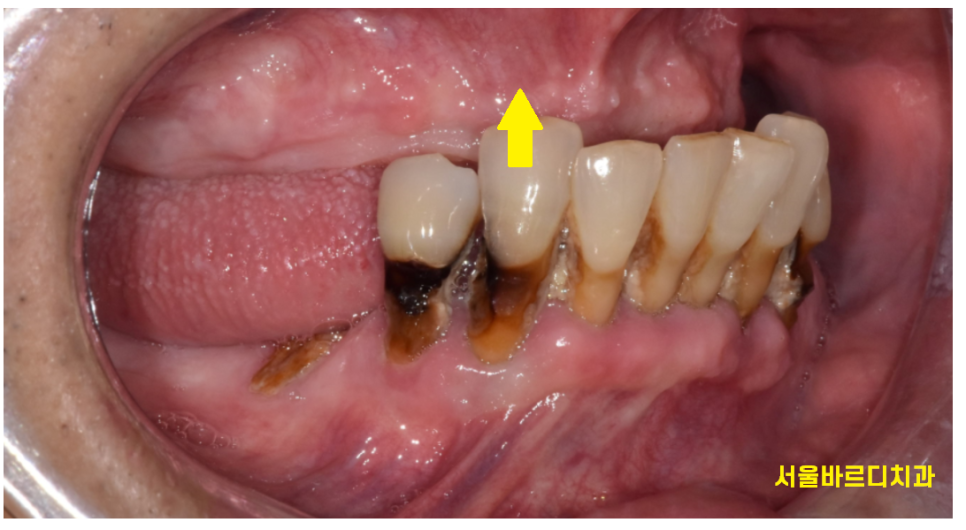

윗니는 치아가 1개도 없는 상태로

"완전 틀니"를 사용하고 계셨습니다.

하나부터 열끝까지 내 치아 말고 가짜이로 살고 계셨다는거죠~

231031

틀니를 안껴도

아래 치아가 위에 잇몸에 닿고 있었거든요~